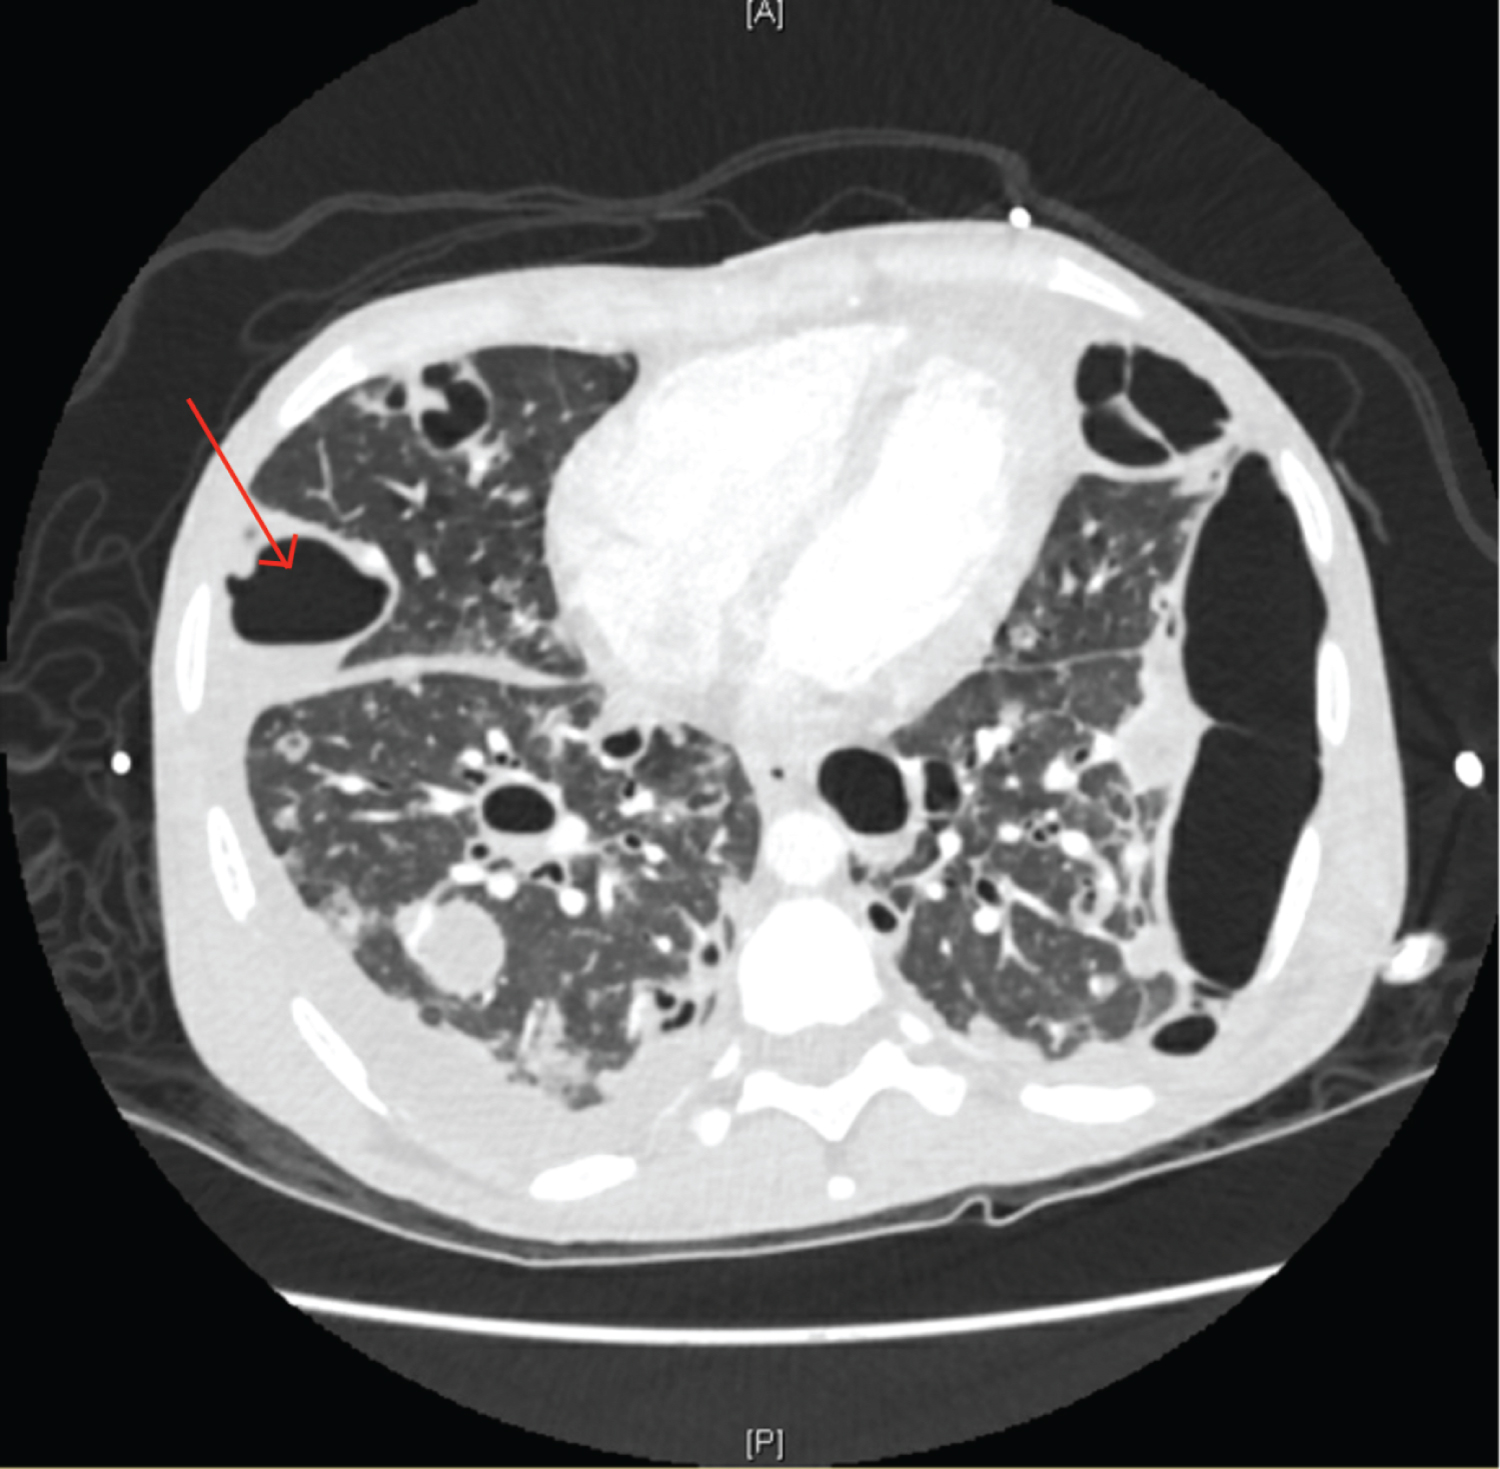

A 29-year-old female with an extensive history of polysubstance abuse presented to an outside hospital for symptoms of myalgias, malaise, and a dry cough for one week in duration. Additional imaging was obtained, most notable for multiple cavitary lung lesions, a possible bronchopleural fistula, and tricuspid valve vegetation. The patient was transferred to our institution for consideration for cardiothoracic surgical intervention. Upon arrival, the patient was found to be hypoxic with an oxygen saturation of 79% on room air, tachypneic, and tachycardic to 130 beats per minute. She presented with altered mentation and was subsequently intubated for worsening respiratory distress. A left lower sternal border diastolic heart murmur and coarse breath sounds on posterior chest auscultation were appreciated. Blood cultures obtained at the previous hospital were positive for methicillin resistant Staphylococcus aureus and reconfirmed on three subsequent sets of repeat blood cultures. CT scan findings were significant for numerous lung cavitating lesions with thickened walls bilaterally (Figures 1, Figure 2, Figure 3, Figure 4 and Figure 5), as well as bilateral renal and splenic hypodensities concerning for infarctions. Echocardiogram revealed tricuspid valve regurgitation and multiple vegetations (Figure 6). Admission complete blood count was significant for leukocytosis with a white blood cell count of 24.2k /uL, thrombocytopenia with a platelet count of 24 k/uL. All of the above findings in conjunction with history were suggestive of cavitary septic emboli from infective endocarditis. The patient developed septic shock due to endocarditis and a right pneumothorax likely secondary to a ruptured cavity (Figure 4). Cardiothoracic surgery evaluated the patient for consideration for tricuspid valve repair and deemed her to not be a surgical candidate given her pulmonary status. After a discussion with the patient's family, the patient was palliatively extubated and the patient unfortunately expired [1,2].

Figure 4: CT scan of the chest with arrow pointing to the cavity that later ruptured. Left sided cavity spanning entire left lung border.

Figure 1: CT scan of the chest at the level of the upper lung lobes.